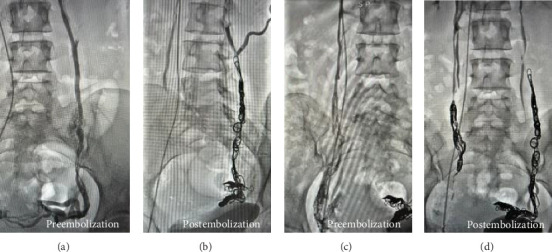

Pelvic congestion syndrome (PCS) is an underdiagnosed but not rare cause of chronic pelvic pain, affecting approximately 10%-30% of women of reproductive age. It is characterized by venous insufficiency and dilation of the ovarian and pelvic veins, often presenting with symptoms that worsen during menstruation or prolonged standing, and improve in the supine position. Dyspareunia and a sensation of pelvic heaviness are also frequently reported. Neurological manifestations-such as pudendal or femoral nerve irritation-are rare but may offer key diagnostic clues. We present a case of a 30-year-old woman with right-sided pelvic pain radiating to the groin and proximal thigh, consistent with neural irritation. Magnetic neurography revealed dilated pelvic veins in close proximity to the right psoas muscle and the L5 nerve root, suggesting perineural venous engorgement. Selective venography confirmed bilateral ovarian vein insufficiency, and the patient underwent successful embolization with Ruby coils and adjunct sclerotherapy. Postoperative recovery was uneventful, with complete resolution of symptoms. Follow-up at 1 year showed no recurrence, and the patient later achieved a successful pregnancy. This case highlights the potential for pelvic venous congestion to mimic or cause neural symptoms and emphasizes the diagnostic value of magnetic neurography in complex pain presentations. Endovascular treatment proved safe and effective, even in cases with neurological involvement.